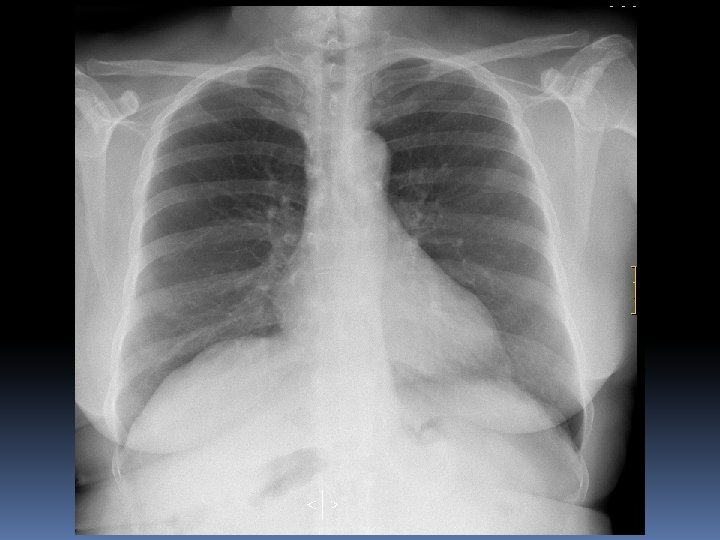

X 2007 Mujer 26 años Astenia, adelgazamiento 5 kg en 3 -4 meses. Nerviosa. Problemas de pareja. Hace 15 dias : tos seca y dolor en costado izquierdo por lo que acude a Urgencias del hospital. No fiebre termometrada. Dolor en costado Izquierdo de características pleuríticas. Auscultación normal. Sat 98%.

90% 20 -35 % 25 %

Desde AP: Laboratorio: puede haber anemia, linfopenia, eosinofilia, trombocitopenia, hipergammaglobulinemia, aumento de VSG, hipercalcemia e hipercalciuria, alteraciones específicas de órganos afectados. En 50 -80% de pacientes se detecta un aumento de la enzima conversora de angiotensina (secretada por fagocitos del granuloma), lo que indica un estadio activo. Hacer serologías para posibles diagnósticos diferenciales. Radiografía de tórax: el 90 -95% de los pacientes tiene alguna alteración radiológica en tórax; lo más frecuente es observar un patrón intersticial retículo-nodular y/o adenopatías hiliares bilaterales. Otros hallazgos posibles son: calcificaciones hiliares “en cáscara de huevo”, cavitación, bronquiectasias, derrame pleural unilateral (exudado linfocitario), cardiomegalia, hipertensión pulmonar. En caso de eritema nodoso con radiología normal y etiología no filiada es conveniente repetir el estudio radiológico al mes.

Clasificación Radiológica.